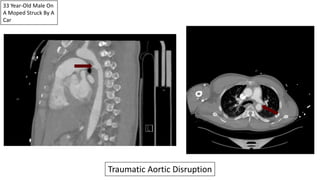

33 Year-Old Male On

A Moped Struck By A

Car

Traumatic Aortic Disruption